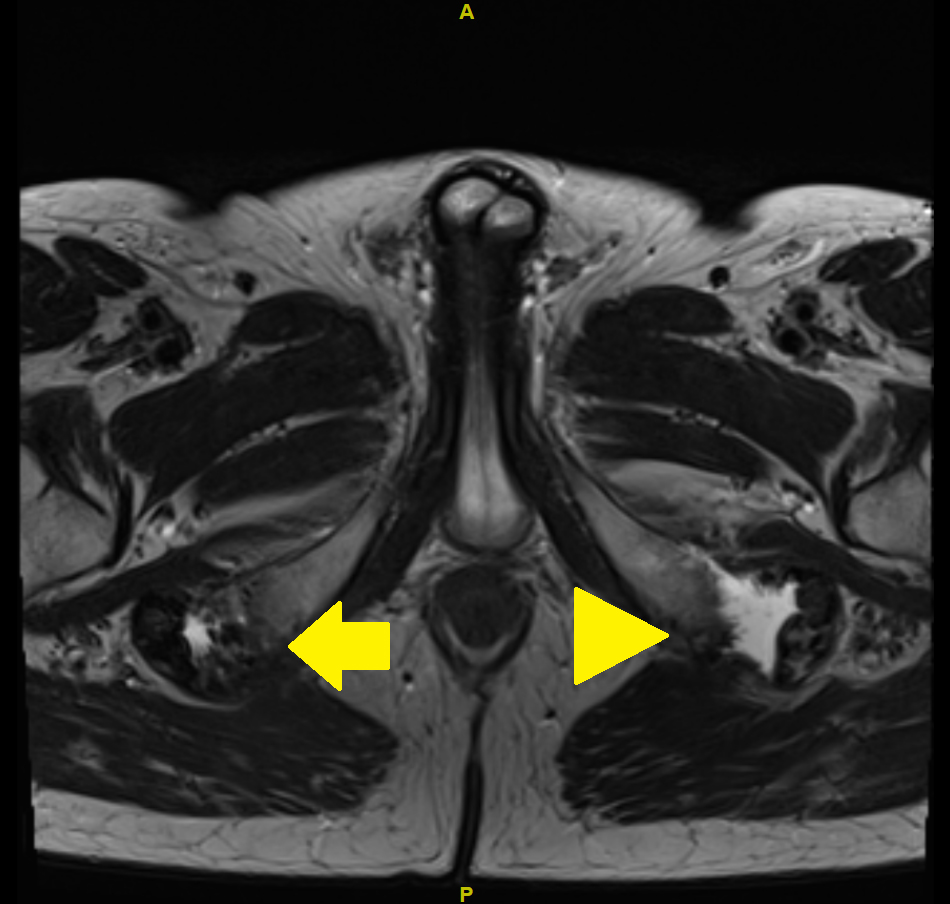

Because of a nonresponse to these measures, magnetic resonance imaging (MRI) of the pelvis was carried out. The MRI showed complete bilateral avulsion of the proximal hamstring muscles with the exception of some remaining fibres of the long head of the biceps femoris muscle on the right side (figs 1—4). There were no clear signs of inflammation nor any signs of myxoid degeneration. Also, there were no signs of inflammation in the area of the hamstring tendons in a past positron emission tomography-computed tomography (PET-CT) performed for melanoma follow up 4 months prior to the MRI.

Figure 2 MRI of the pelvis with T2 turbo spin echo (TSE) weighted image: axial view. Arrow: partial avulsion on the right side; arrowhead: complete avulsion on the left side.